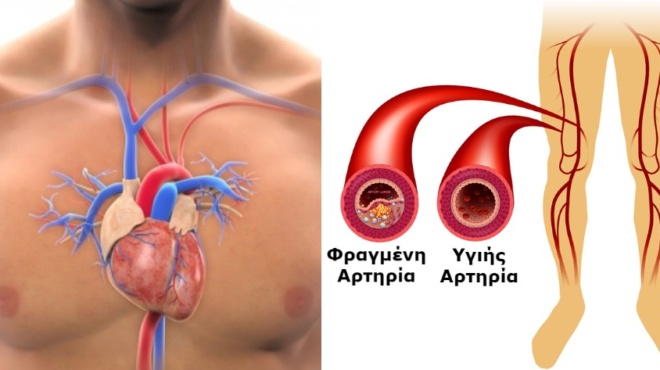

Αρτηρίες όταν είναι φραγμένες σημαίνει ότι έχουν συσσωρευτεί στα τοιχώματά τους λιπαρές ουσίες. Η κατάσταση για τον ασθενή χαρακτηρίζεται ως επικίνδυνη. Είναι “σιωπηλή” και δεν προκαλεί εμφανή σημάδια και συμπτώματα. Συχνά περνά απαρατήρητη μέχρι να προκαλέσει επιπλοκές όπως ένα έμφραγμα ή ένα εγκεφαλικό επεισόδιο.

Βασική αιτία είναι φυσικά οι φραγμένες αρτηρίες που εμποδίζουν τη ροή του αίματος και κουράζουν την καρδιά.

Πόνος στην γάμπα όταν περπατάτε

Η αρτηριοσκλήρωση μπορεί να μπλοκάρει τις αρτηρίες των ποδιών, ιδιαίτερα στους καπνιστές, προτού καν διαγνωστεί σε αυτούς στεφανιαία νόσος. Αυτό το σύμπτωμα απαιτεί άμεση ιατρική αξιολόγηση χωρίς καθυστέρηση.

Ο γιατρός σας θα εξετάσει τους παλμούς στα πόδια σας και θα εκτελέσει απλές μετρήσεις της αρτηριακής πίεσης των ποδιών και της ροής του αίματος για να επιβεβαιωθεί η διάγνωση της κακής κυκλοφορίας στα πόδια.

Η απόφραξη των αρτηριών ονομάζεται στον ιατρικό χώρο αθηροσκλήρωση. Η αθηροσκλήρωση χαρακτηρίζεται από τη συσσώρευση ουσιών στα εσωτερικά τοιχώματα των αρτηριών και αποτελεί την αιτία της στεφανιαίας νόσου και άλλων κυκλοφορικών προβλημάτων.

Η αθηροσκλήρωση μπορεί να προσβάλει οποιαδήποτε αρτηρία του σώματος, παρατηρείται όμως κυρίως σε αυτές που διοχετεύουν αίμα στην καρδιά (στεφανιαίες), στις αρτηρίες του λαιμού που διοχετεύουν αίμα στον εγκέφαλο (καρωτίδες) και στις αρτηρίες των ποδιών (περιφερικές).

Η δημιουργία της αθηρωματικής πλάκας, όπως ονομάζεται η συμπαγής μάζα στο εσωτερικό των αρτηριών, συμβαίνει σε βάθος πολλών ετών, ξεκινώντας από νεαρή ακόμη ηλικία.